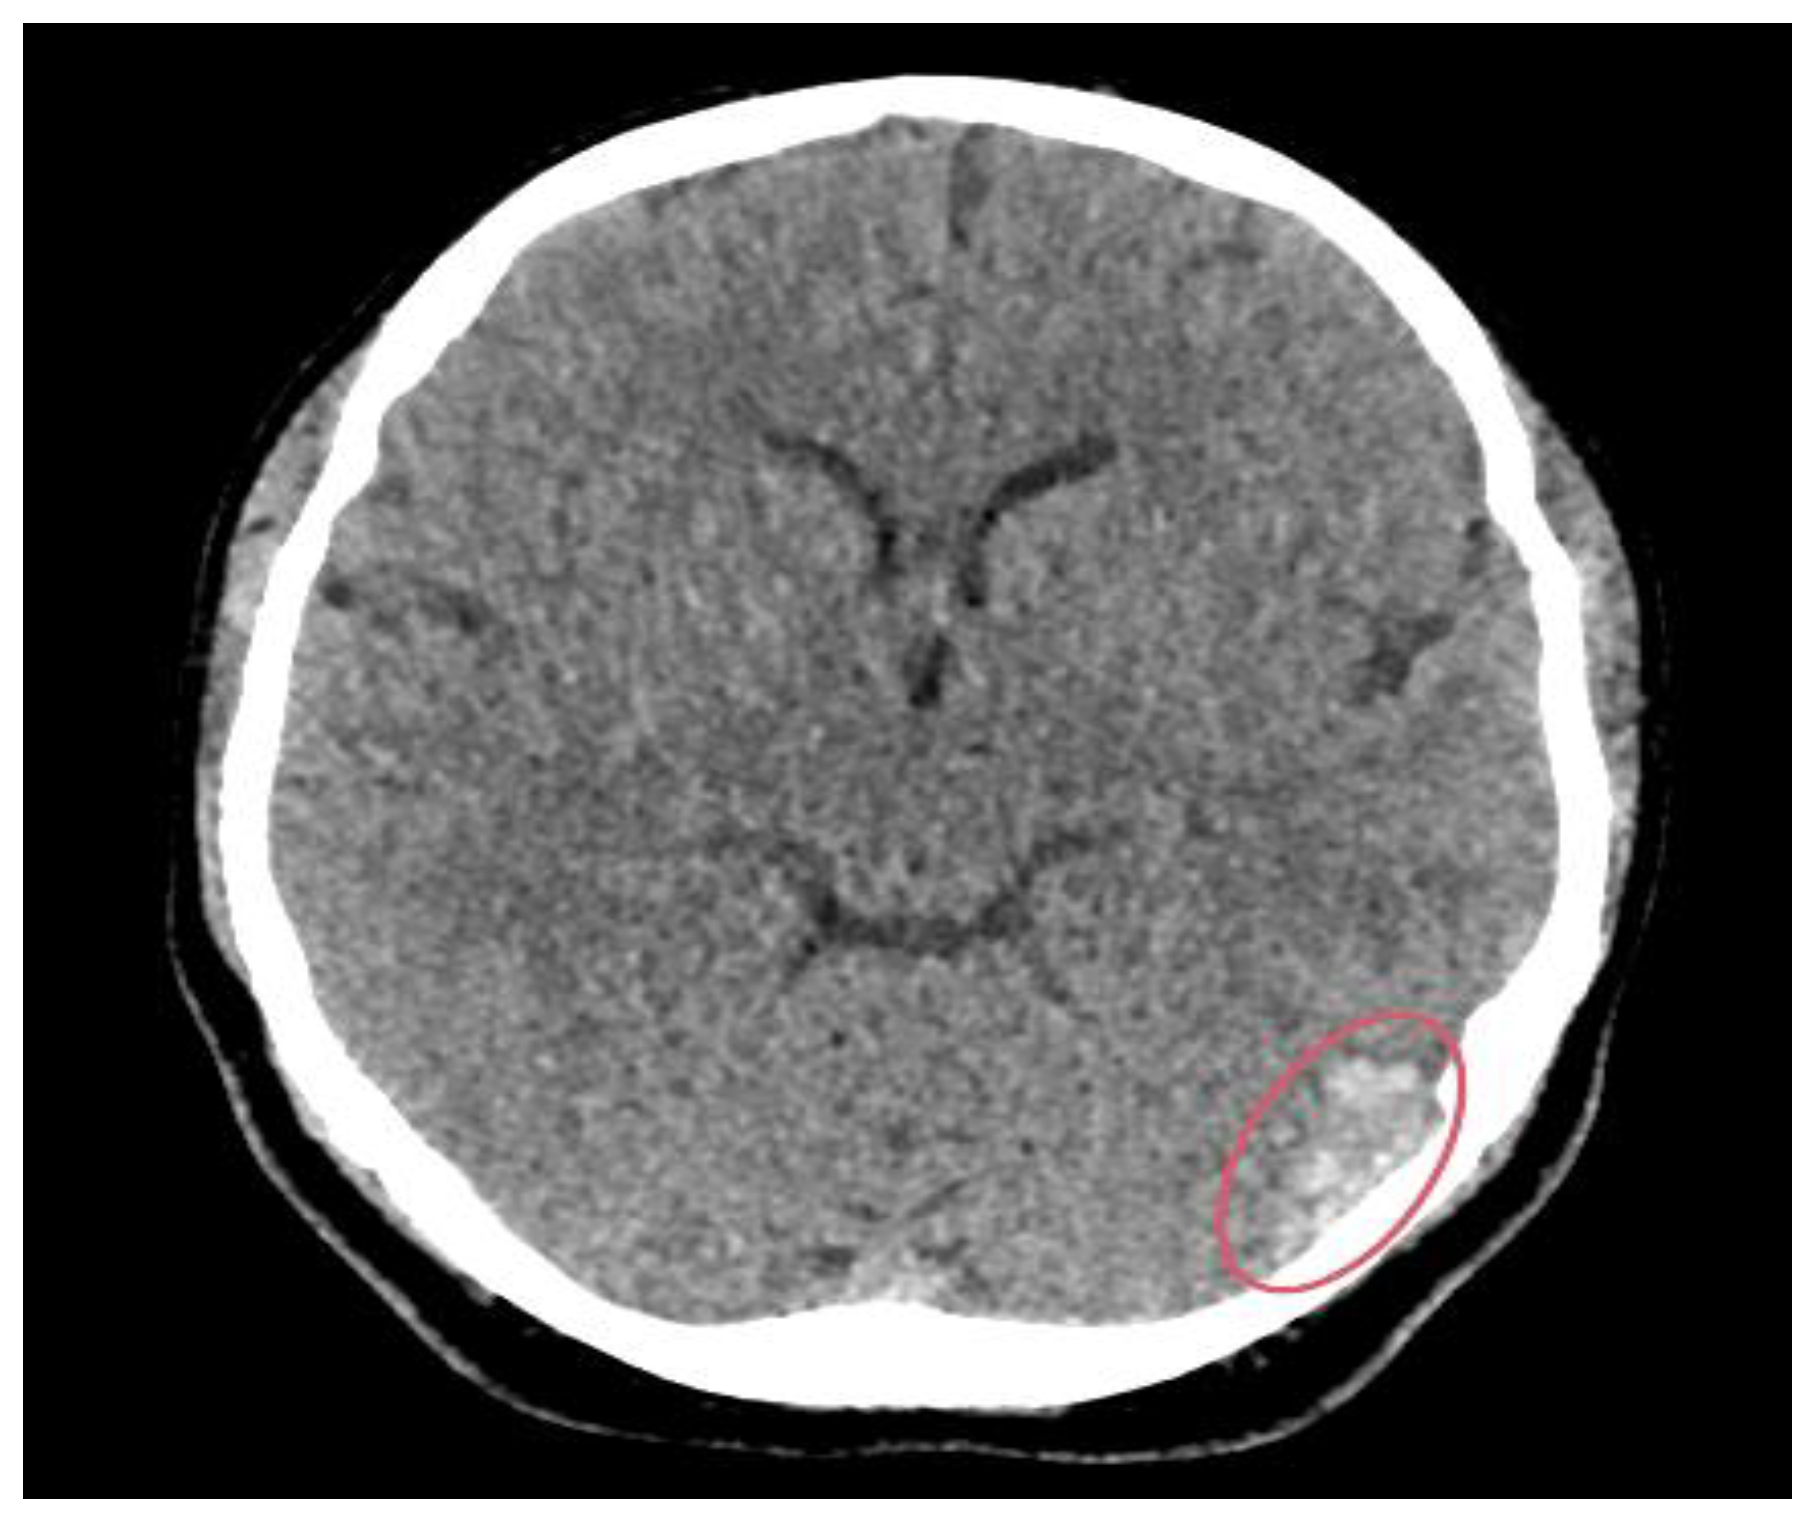

3.2. Imaging Role